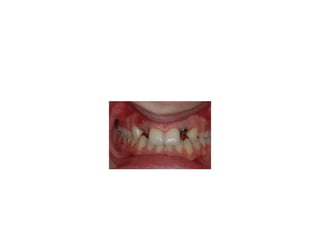

pre-op